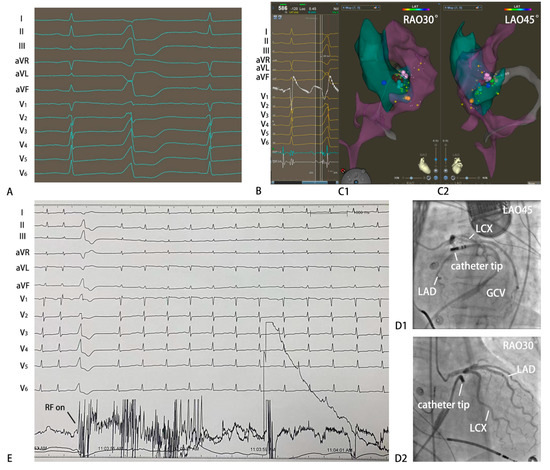

3.2. Electrophysiological Study and Radiofrequency Catheter Ablation

3.5. RV1/RV2 Ratio Diagnosed VAs Originating from the Epicardial Anterolateral Portion Adjacent to MA

3.6. IDT and MDI Predicted the VAs Arising from the Epicardium

3.7. Q(q)R(r) Morphology in Lead V1 Predicted the VAs Arising from the Endocardial Septal Wall Adjacent to the MA